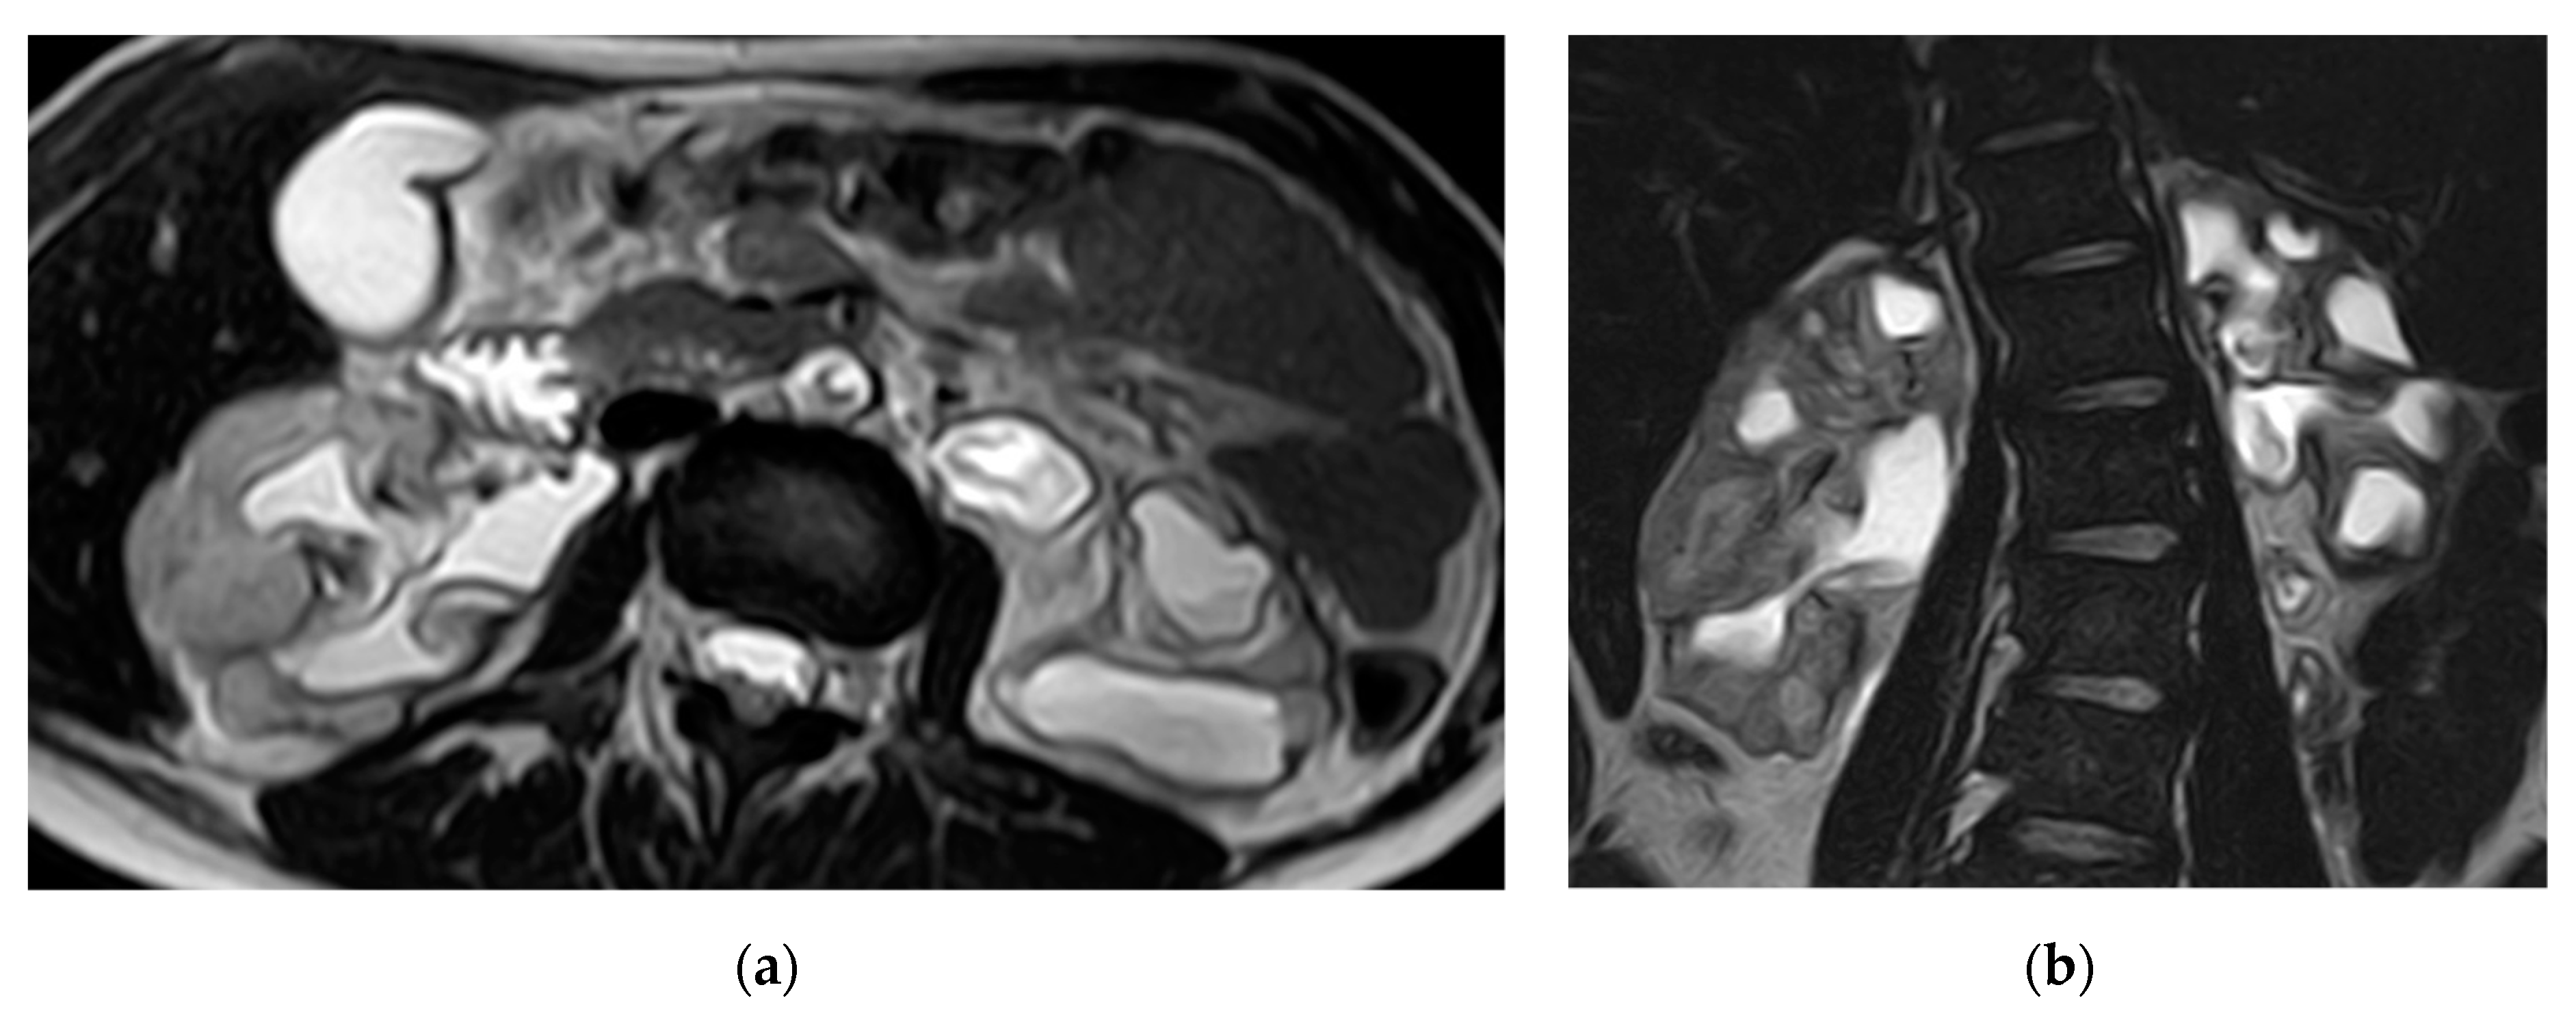

2.5. Xanthogranulomatous Pyelonephritis (XGP)

| Xanthogranulomatous Pyelonephritis | Non-functioning enlarged kidney, obstructing stone within a non-dilated renal pelvis, expansion of the calyces, and inflammatory changes in the perinephric fat. |